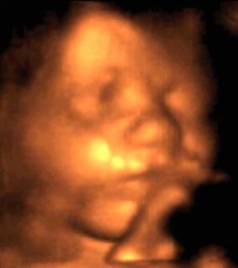

More 4D photos, and Amelie's first home movie. Shirley Temple eat your heart out.

She starts by sticking her tongue out. It was a sign of things to come.